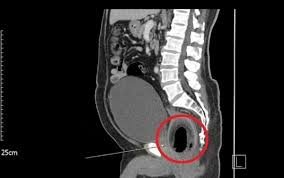

Um homem de 53 anos foi internado na noite dessa terça-feira (27) no Hospital de Trauma de João Pessoa após dar entrada com um coco inserido no ânus.

Segundo a equipe médica, o paciente apresentava sangramento intenso e dores severas.

O coco foi retirado por meio de cirurgia ainda na mesma noite.